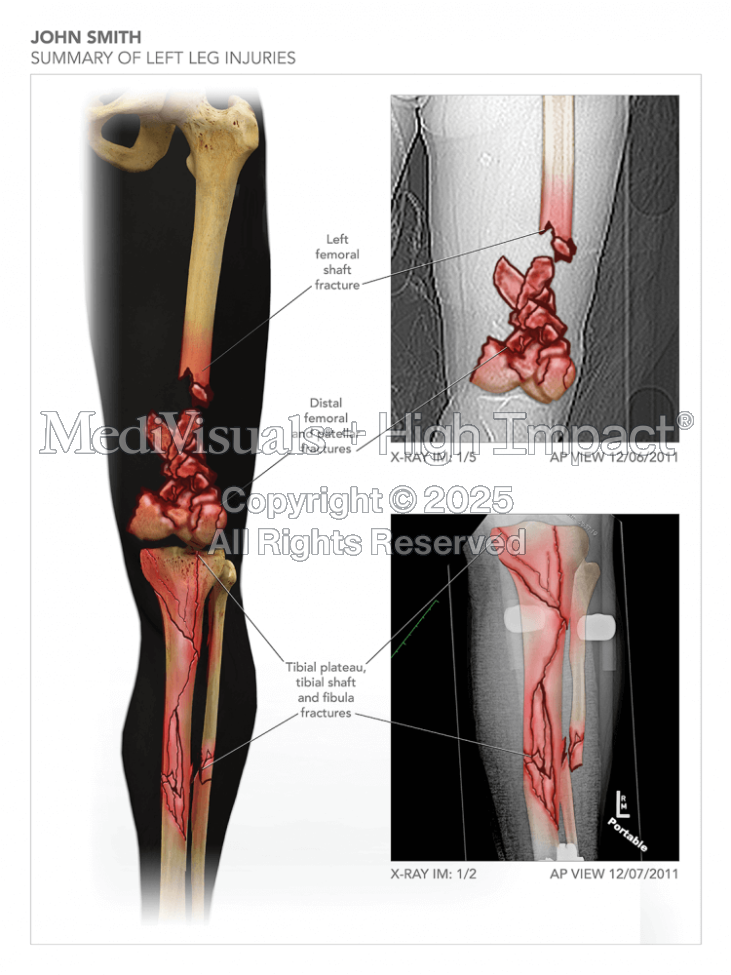

Summary of Left Leg Injuries

Available in high resolution JPEG or PDF formats, 8x10 print, or laminated foam core exhibit board (24x46, 30x40 or 36x48).